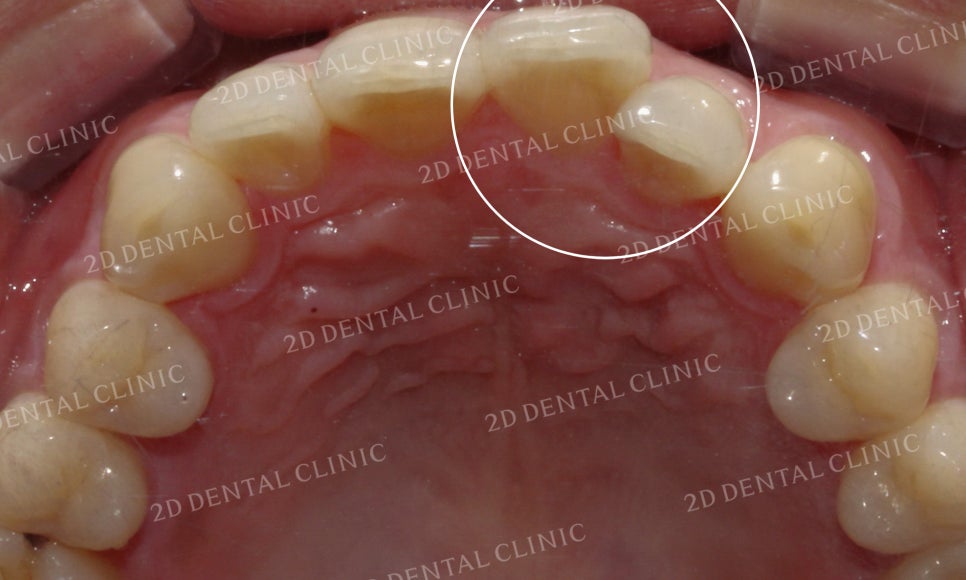

상악 설측면의 사진입니다.

위에서 말했던 것처럼

21번 치아가 회전되어 있어서

측정치가 설측으로 들어와 있는

상황입니다.

상악의 설측면 사진입니다.

표시된 부분의 21번 치아가

유독 회전이 심한 모습이었는데요

이로 인해 측절치가 중절치의

뒤쪽으로 파고들면서

치간에 치석과 플라그가 쌓이고 있는 상태였습니다.

그러나 교정 후 치아가 겹쳐진 부분들이 사라지고

삐뚤거리던 크라우딩도 사라지면서

가지런해진 치아들을 볼 수 있습니다.